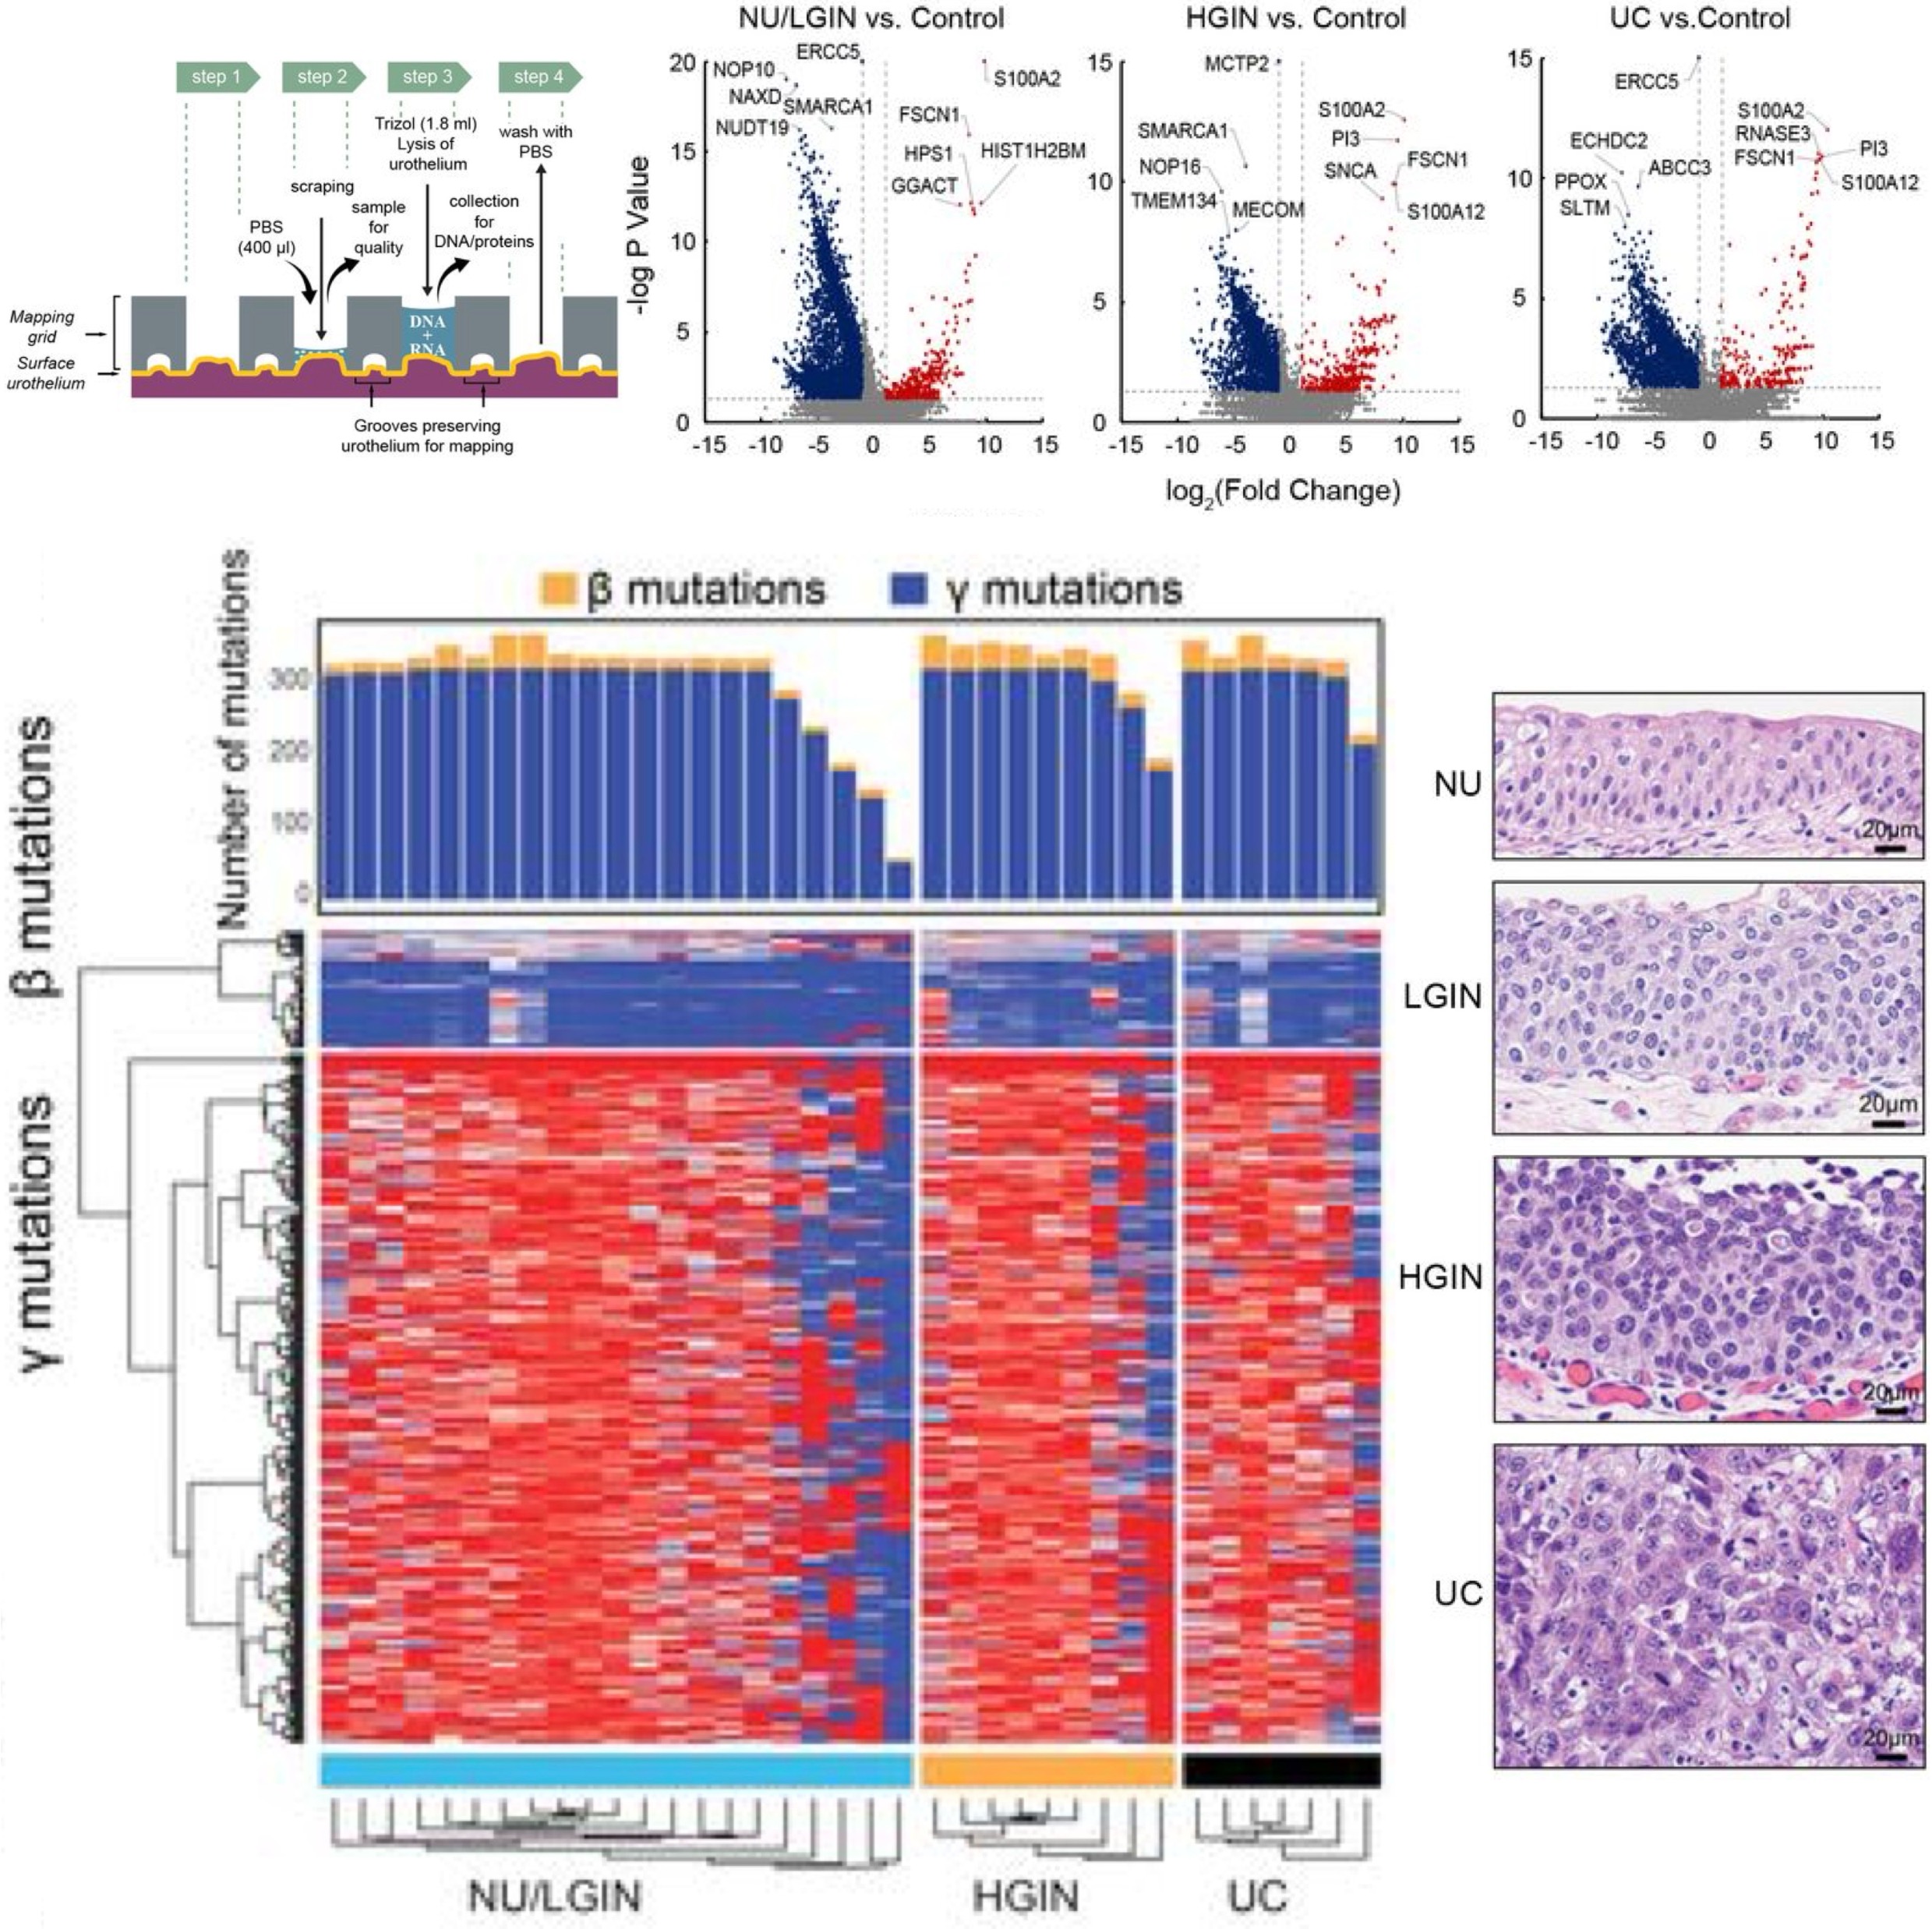

Dysregulated mitochondrial energy metabolism drives the progression of mucosal field effects to invasive bladder cancerSangkyou Lee, Sung Yun Jung, Pawel Kuś, Jolanta Bondaruk, June Goo Lee, Roman Jaksik, Nagireddy Putluri, Khanh N. Dinh, David Cogdell, Huiqin Chen, Yishan Wang, Jiansong Chen, Neema Navai, Colin Dinney, Cathy Mendelsohn, David McConkey, Richard R. Behringer, Charles C. Guo, Peng Wei, Marek Kimmel, and Bogdan CzerniakThe Journal of Pathology. Highlighted in Nature Reviews Urology , 2025

Dysregulated mitochondrial energy metabolism drives the progression of mucosal field effects to invasive bladder cancerSangkyou Lee, Sung Yun Jung, Pawel Kuś, Jolanta Bondaruk, June Goo Lee, Roman Jaksik, Nagireddy Putluri, Khanh N. Dinh, David Cogdell, Huiqin Chen, Yishan Wang, Jiansong Chen, Neema Navai, Colin Dinney, Cathy Mendelsohn, David McConkey, Richard R. Behringer, Charles C. Guo, Peng Wei, Marek Kimmel, and Bogdan CzerniakThe Journal of Pathology. Highlighted in Nature Reviews Urology , 2025Multiplatform mutational and gene expression profiling complemented with proteomic and metabolomic spatial mapping were used on the whole-organ scale to identify the molecular profile of bladder cancer evolution from field effects. Analysis of the mutational landscape identified three types of mutations, referred to as alpha, beta, and gamma. Time modeling of the mutations revealed that carcinogenesis may span 30 years and can be divided into dormant and progressive phases. The alpha mutations developed in the dormant phase. The progressive phase lasted 5 years and was signified by expanding beta mutations, but it was driven to invasive cancer by gamma mutations. The mutational landscape emerged on a background of disorganized urothelial differentiation, activated epithelial-mesenchymal transition, and enhanced immune infiltration with T-cell exhaustion. Complex dysregulation of mitochondrial energy metabolism with downregulation of oxidative phosphorylation emerged as the leading mechanism driving the progression of mucosal field effects to invasive cancer.

The origin of bladder cancer from mucosal field effectsJolanta Bondaruk, Roman Jaksik, Ziqiao Wang, David Cogdell, Sangkyou Lee, Yujie Chen, Khanh N. Dinh, Tadeusz Majewski, Li Zhang, Shaolong Cao, Feng Tian, Hui Yao, Pawel Kuś, Huiqin Chen, John N. Weinstein, Neema Navai, Colin Dinney, Jianjun Gao, Dan Theodorescu, Christopher Logothetis, Charles C. Guo, Wenyi Wang, David McConkey, Peng Wei, Marek Kimmel, and Bogdan CzerniakiScience, 2022

The origin of bladder cancer from mucosal field effectsJolanta Bondaruk, Roman Jaksik, Ziqiao Wang, David Cogdell, Sangkyou Lee, Yujie Chen, Khanh N. Dinh, Tadeusz Majewski, Li Zhang, Shaolong Cao, Feng Tian, Hui Yao, Pawel Kuś, Huiqin Chen, John N. Weinstein, Neema Navai, Colin Dinney, Jianjun Gao, Dan Theodorescu, Christopher Logothetis, Charles C. Guo, Wenyi Wang, David McConkey, Peng Wei, Marek Kimmel, and Bogdan CzerniakiScience, 2022Whole-organ mapping was used to study molecular changes in the evolution of bladder cancer from field effects. We identified more than 100 dysregulated pathways, involving immunity, differentiation, and transformation, as initiators of carcinogenesis. Dysregulation of interleukins signified the involvement of inflammation in the incipient phases of the process. An aberrant methylation/expression of multiple HOX genes signified dysregulation of the differentiation program. We identified three types of mutations based on their geographic distribution. The most common were mutations restricted to individual mucosal samples that targeted uroprogenitor cells. Two types of mutations were associated with clonal expansion and involved large areas of mucosa. The αmutations occurred at low frequencies while the βmutations increased in frequency with disease progression. Modeling revealed that bladder carcinogenesis spans 10-15 years and can be divided into dormant and progressive phases. The progressive phase lasted 1-2 years and was driven by βmutations.